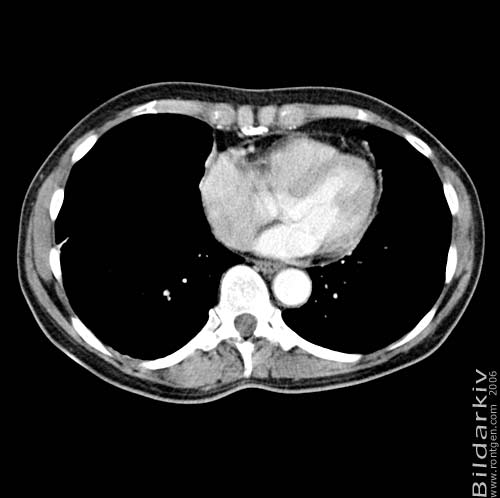

Thorax 41

Snitt över thorax med kontrast. Sk. mediastinum-fönstersättning.

CT Röntgen Helsingborgs lasarett

Mediastinum